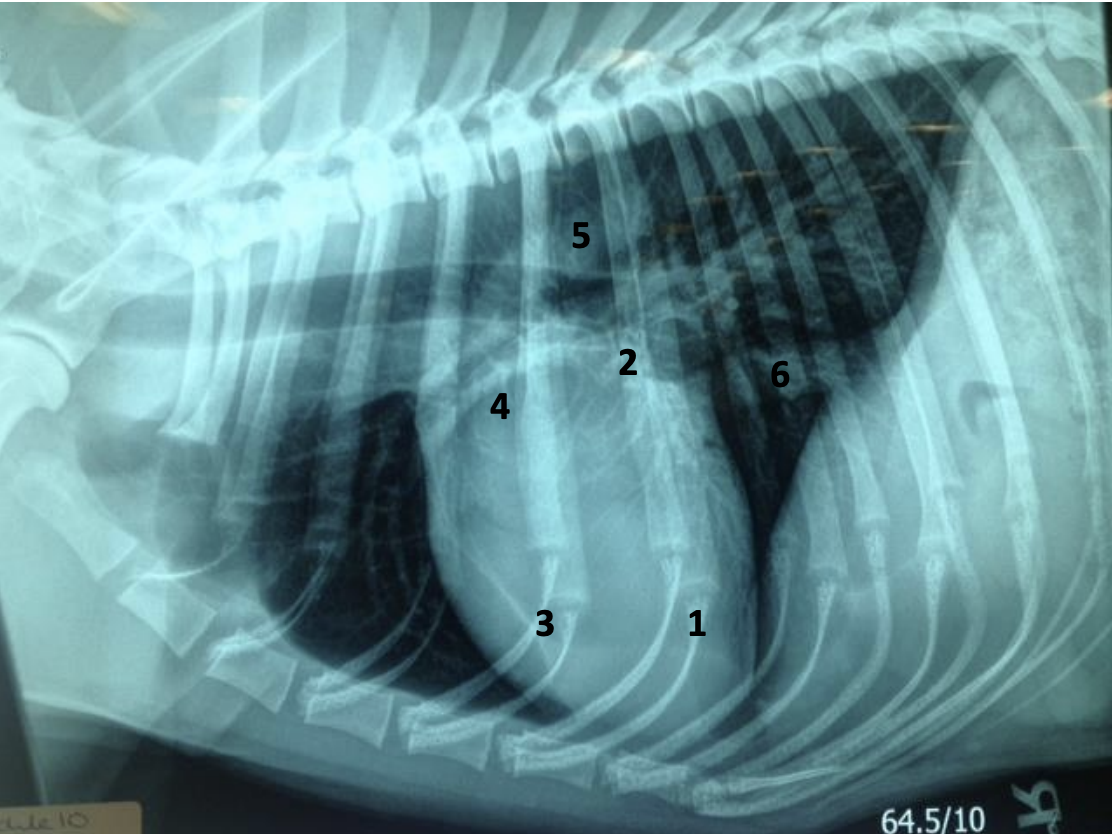

What is the vertebral heart score in this dog and how would you assess its heart relative to the intercostal spaces and height of the thorax? Is this dog normal?

VHS approx 12. Heart slightly greater than 2/3 height and width of thorax. Suggested slightly enlarged

Why do the lung lobes appear dark on radiographs?

Air filled therefore do not attenuate the X-Ray bean resulting in increased blackening of the film – described as being radiolucent

Why are the blood vessels in the lung visible?

They are a combination of fluid (blood) and soft tissue (vessel walls) and so are radio-opaque (grey) while the surrounding lung is air filled and therefore radiolucent (dark)